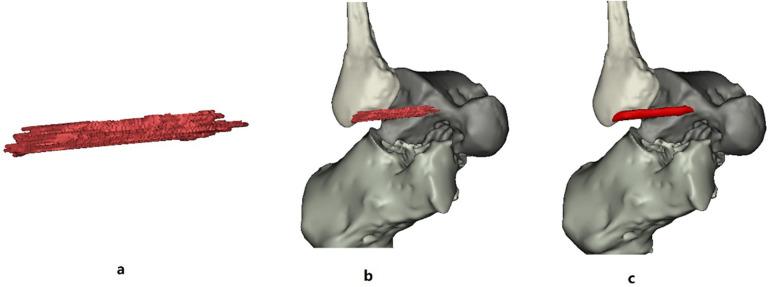

METHODS

A total of 21 healthy asymptomatic volunteers with 30 normally functioning ankles and 13 patients with 18 sprained ankles were studied. MRI scans were divided into two groups: Group 1 (normal ankle) and Group 2 (injured ankle). The data of all 48 cases were exported to Mimics and reconstructed into 3D models. The image quality of all 3D models was evaluated using a 5-point subjective scoring system. The length, width, and thickness of the ATFL were measured in the 3D model in Mimics and compared to the 3D MPR image data.

The image quality score was 4.57 ± 0.32. There was no statistically significant difference between the 3D model and the 3D MPR image of ATFL measurements in both groups ( > 0.05).

We concluded that 3D MRI can be used to reconstruct a 3D model of the ATFL for accurate measurements of the ATFL anatomical structure, which holds potential to improve preoperative planning and intraoperative navigation for young sports medicine doctor, facilitate diagnosis of ATFL injuries and make the decision about the operative method.